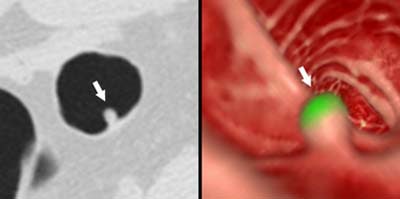

![]() |

| Above, false-positive finding due to a prominent fold. On axial image, the tip of the fold (arrow) appears to be a polyp-like structure, which led to its being incorrectly identified as a polyp. Image courtesy of Dr. Abraham Dachman. |

| Above, false-positive finding due to retained solid stool. The round appearance and the solid internal structure mimic a polyp. Image courtesy of Dr. Abraham Dachman. |

"All of the false-positives had at least one lesion that had a caplike shape…mimicking the appearance of a polyp," Dachman said, noting that further analysis of the caplike shape algorithm significantly improved the results. In addition, most of the false positives due to stool had solid internal structures, he said.

"Most (87%) of the CAD false positives can be easily identified by the human observer," Dachman concluded. "Reliable identification and removal of folds and stool has the potential to reduce false positives by 70%."